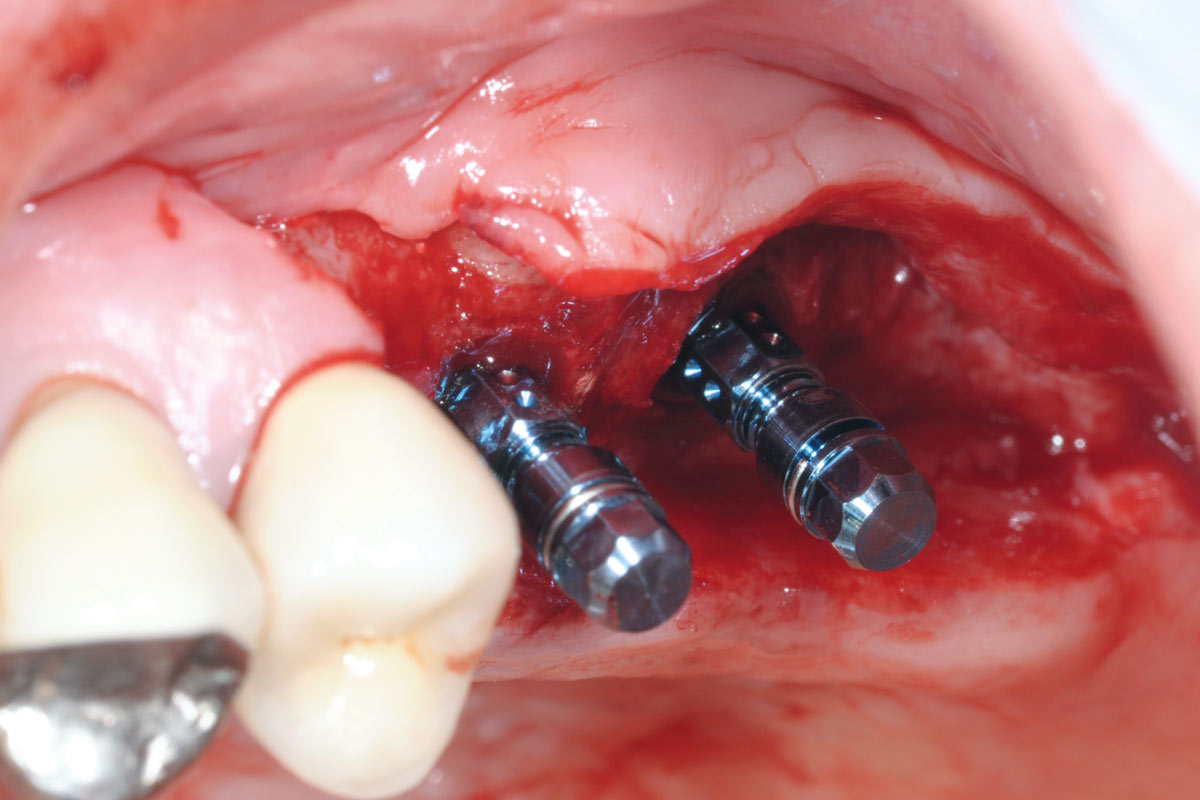

10/15 - Insertion of two Straumann Bone Level Tapered implants 4.8, 10 mm, lateral viewTreatment of a combined horizontal and vertical bone defect in the maxilla with maxgraft® cortico in the allogenic shell technique - Dr. R. Würdinger